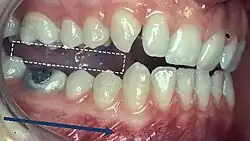

When describing the relationship between maxillary and mandibular incisors, the following categories make up Angle's incisal relationship classification:

- Class I: Mandibular incisors contact the maxillary incisors in the middle third or on the cingulum of the palatal surface

- Class II: Mandibular incisors contact the maxillary incisors on the palatal surface, in the gingival third or posterior to the cingulum. This class may be further subdivided into division I and division II:

- Class III: Mandibular incisors occlude with the maxillary incisors on the palatal surface, in the incisal third specifically or anterior to the cingulum

- In some cases the overjet is reversed (<0mm) and the mandibular incisors lie anterior to the maxillary incisors